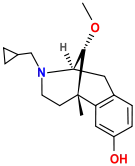

Oripavine derivatives

Thienorphine

- 7-PET

- Acetorphine

- Alletorphine (N-allyl-noretorphine)

- BU-48

- Buprenorphine

- Buprenorphine-3-glucuronide

- Cyprenorphine

- Dihydroetorphine

- Etorphine

- Homprenorphine

- 18,19-Dehydrobuprenorphine (HS-599)

- N-cyclopropylmethylnoretorphine

- Nepenthone

- Norbuprenorphine

- Norbuprenorphine-3-glucuronide

- Thevinone

- Thienorphine

Structures

| Oripavine derivatives | ||||

|---|---|---|---|---|

7-PET 7-PET |

Acetorphine Acetorphine |

Alletorphine Alletorphine |

BU-48 BU-48 |

Buprenorphine Buprenorphine |

Cyprenorphine Cyprenorphine |

Dihydroetorphine Dihydroetorphine |

Etorphine Etorphine |

Homprenorphine Homprenorphine |

18,19-Dehydrobuprenorphine 18,19-Dehydrobuprenorphine |

N-cyclopropylmethylnoretorphine N-cyclopropylmethylnoretorphine |

Nepenthone Nepenthone |

Norbuprenorphine Norbuprenorphine |

Thevinone Thevinone |

Thienorphine Thienorphine |